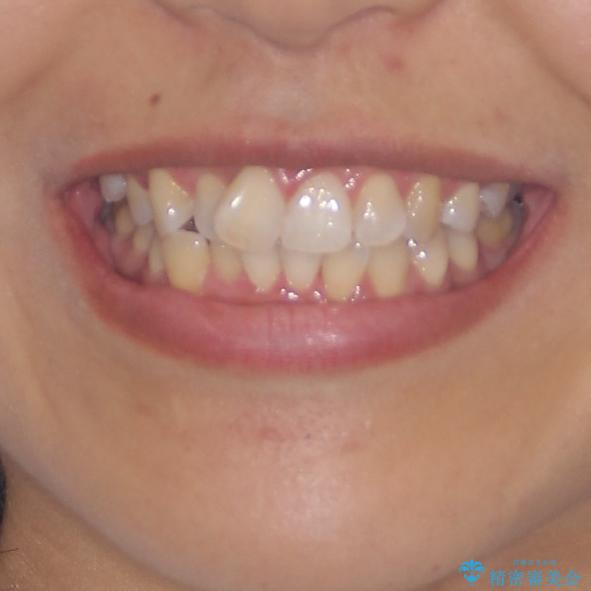

前歯のデコボコをインビザラインでスッキリと仕上げる

長時間のマウスピース装着に協力いただき、自然な口元に仕上げることができました。

気になっていた銀歯もオールセラミッククラウンで本物の歯のようになり、患者様には大変満足していただきました。